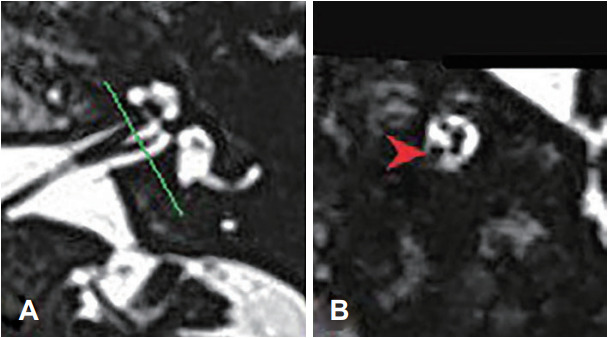

Abstract Image